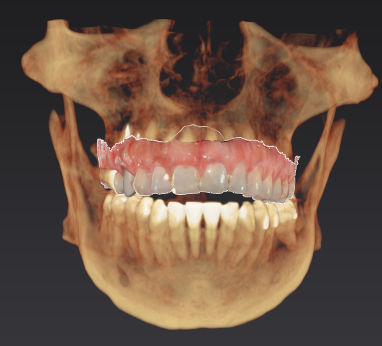

Intraoral scanning uses a small handheld device to capture detailed digital images of your teeth and gums, which are then processed into an incredibly precise 3D model of your mouth. This quick and comfortable process eliminates the need for messy impression materials, providing instant results that you and your dentist can view together in real time.

High-precision scans result in better-fitting restorations and more accurate planning for treatments such as crowns, bridges, implants, and orthodontics. With faster turnaround times, improved communication, and an eco-friendly digital workflow, intraoral scanning enhances both comfort and efficiency throughout your dental care.

Surgical Guides for Dental Implant Placement

Surgical guides are custom-made tools created from digital scans or 3D images that help dentists and oral surgeons place dental implants with exceptional precision and safety. By guiding the surgeon’s instruments during the procedure, they allow for ideal implant positioning, shorter surgery times, and a more minimally invasive experience with reduced swelling and discomfort.

This accuracy leads to faster recovery, fewer complications, and better long-term outcomes including well-fitting restorations that feel natural and function properly. Patients can support their results by discussing surgical guide options with their dentist, reviewing digital plans, and closely following all pre- and post-operative instructions.